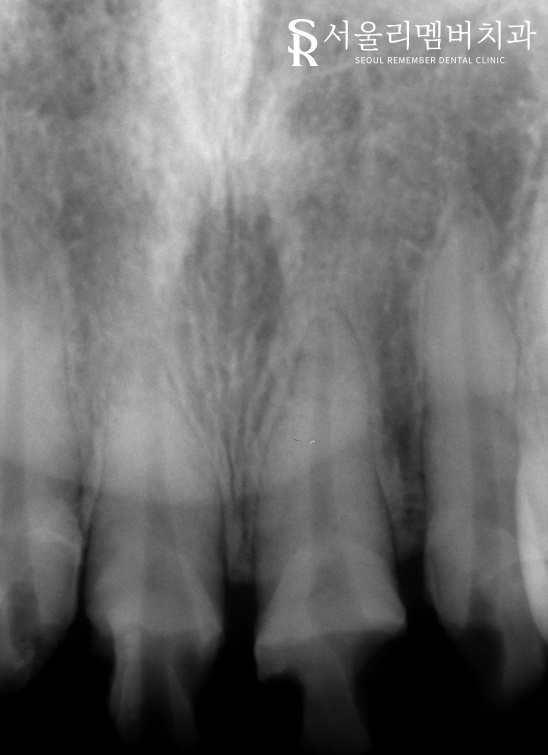

치근단 사진을 촬영해 보니

뿌리 주변으로도 염증이 생겨

상황이 좋지 않은 것을 알 수 있었는데요.

서울대입구역치과 에서는

신경치료를 진행하여 현재 나타난 문제들을

개선해야겠다는 판단이 들었습니다.